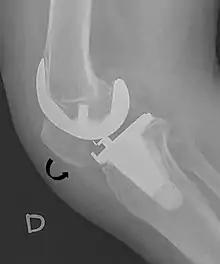

Dislocation

Patellar dislocations occur with significant regularity, particularly in young female athletes.[2] It involves the patella sliding out of its position on the knee, most often laterally, and may be associated with extremely intense pain and swelling.[3] The patella can be tracked back into the groove with an extension of the knee, and therefore sometimes returns into the proper position on its own.[3]

- Melloni, Pietro; Veintemillas, Maite; Marin, Anna; Valls, Rafael (2013). "Imaging Patellar Complications After Knee Arthroplasty". Arthroplasty - Update. doi:10.5772/53666. ISBN 978-953-51-0995-2. (CC-BY-3.0)